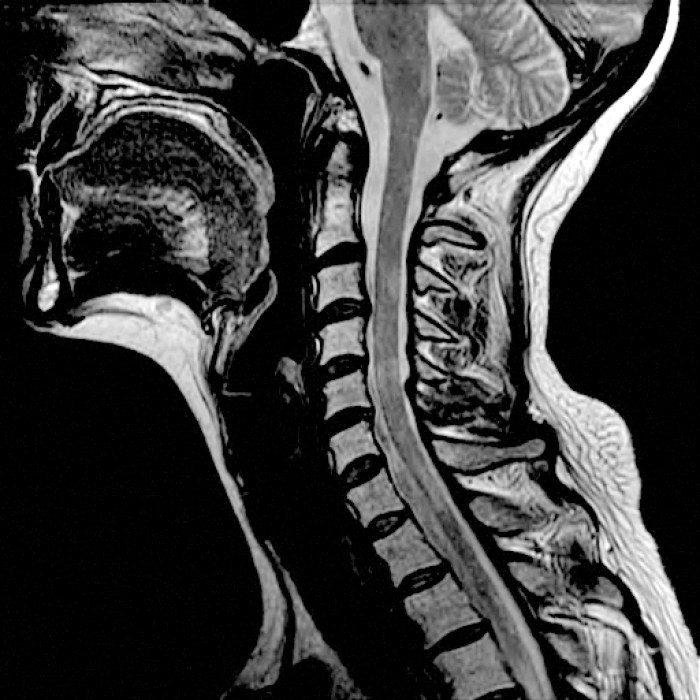

My doctor told me the other day that I have Secondary Progressive. “You have permanent damage in your spinal cord.” Multiple Sclerosis (MS) is a disease in which the body’s immune system attacks the protective covering surrounding the nerves of the central nervous system.

So now, it’s been seven years since I’ve been off western medicine and my doctor tells me I have permanent spinal cord damage (with demyelination lesions on my spinal cord) and that is why I can not walk more than a mile. After two miles my left leg just stops working. The past seven years have been the happiest years of my life. My first thought when I was in the doctor’s office listening to her was “I know you are going to suggest some sort of treatment plan.” So as I previously stated I went off western medicine in 2009; it took about 4 years for my headaches to go away (holistic healing doesn’t always happen quickly). My last headache was in January 2013. Because I really can’t walk more than 3 miles without falling over, I was interested in hearing what she had to say. “With this stage of MS, there are not a lot of options. And most medication plans are 50% chance of you walking better.” Haa!